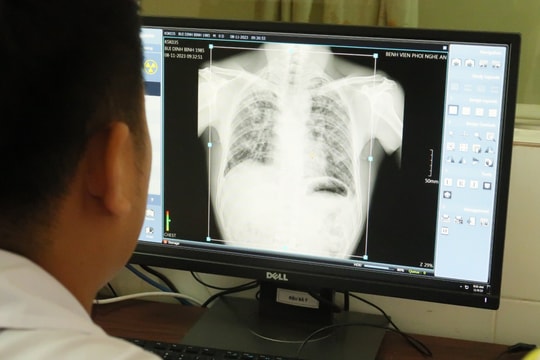

Qua kết quả khám, phát hiện bệnh nghề nghiệp, có 62 lao động đã và đang làm việc tại đây mắc bệnh bụi phổi silic nghề nghiệp, trong đó: 5 người chết liên quan đến bệnh bụi phổi silic, 1 trường hợp tử vong chưa xác định nguyên nhân cụ thể, 19 người lao động bị mắc bệnh bụi phổi silic nặng, 25 người mức độ mắc bệnh trung bình, 13 người mức độ tổn thương trên phổi cần theo dõi và 20 trường hợp khám đợt 3 chưa có kết quả.

Các trường hợp làm việc tại công ty khám nhưng không mắc bệnh nghề nghiệp chủ yếu là cán bộ quản lý, lao động gián tiếp trong văn phòng. Các trường hợp lao động còn lại đang tiếp tục được rà soát, khám phát hiện bệnh nghề nghiệp, nguy cơ số người mắc khả năng cao sẽ tăng. Các trường hợp mắc bệnh bụi phổi mức độ nặng có nguy cơ suy giảm sức khỏe nhanh, khả năng tử vong cao. Các trường hợp trung bình cũng có nguy cơ tăng nặng nếu không được điều dưỡng, phục hồi chức năng đầy đủ.